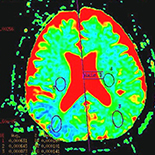

Magnetic resonance angiography (MRA) and diffusion-weighted imaging (DWI) have been widely used in the prediction of ischemic stroke; however, the differences of the 2 methods in detection the artery lesion differences between transient ischemic attack (TIA) and infarction patients have been long neglected. We performed the present study to investigate the differences between vessel characteristics detected by MRA and DWI in acute stroke and TIA patients.

We classified 110 subjects into 2 groups and all the patients underwent both MRA and DWI. The degree of stenosis of cranial and cervical arteries, the distribution of the stenosis, the development and changes of the vessels, and the DWI scanning results of the brain tissue were all analyzed.

We detected a significant difference in the number and the degree of stenosis of cranial and cervical arteries among the 3 groups (P=0.006). Compared with health controls, patients with TIA and cerebral infraction had much more severe stenosis and occlusive arteries (P<0.05). However, no significant difference was detected between TIA and cerebral infraction patients (P=0.148). Moreover, a higher rate of unilateral vertebral artery dysplasia was found in the vertebrobasilar TIA patients. Higher lesion signals were also observed by DWI in TIA patients of internal carotid artery system (4/8, 50%).

Vessel characteristics were not significantly different between TIA and infarction patients. Unilateral vertebral artery hypoplasia was a predisposing factor for vertebrobasilar TIA and ischemic focus in DWI detection was always caused by severe artery lesions.